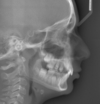

La téléradiographie de profil

La téléradiographie de profil est un examen indispensable en orthodontie :

- Elle permet d'avoir une vision de l'ensemble du visage, et notamment des positions des mâchoires supérieure et inférieure au sein de la face.

Elle est particulièrement utile lorsqu'il existe un décalage antéro postérieur entre les deux arcades.

- Elle permet également de visualiser le profil cutané et d'étudier les rapports entre nez, lèvres et menton.

- Elle permet enfin d'apprécier la direction de croissance faciale.

La téléradiographie est un examen que nous réalisons sur place au cabinet.